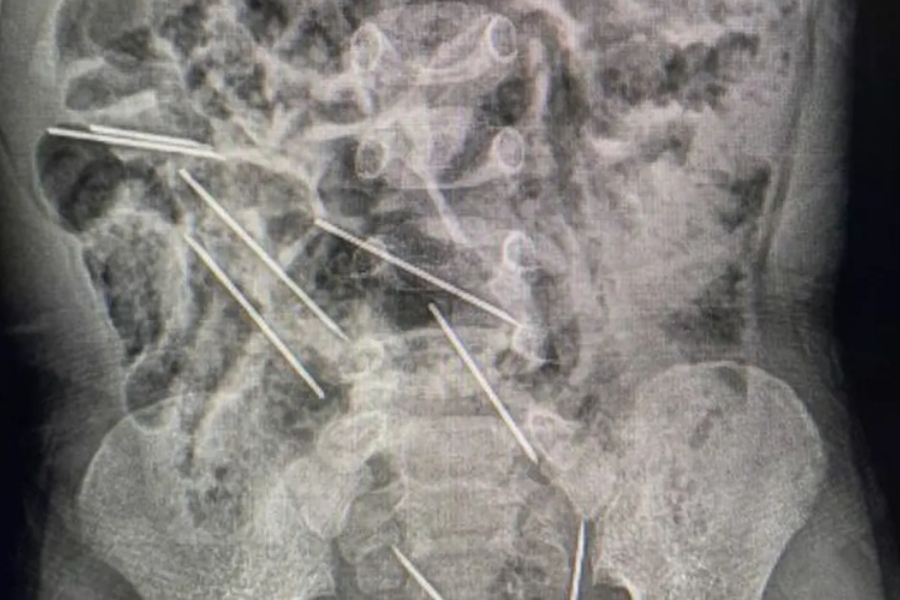

Según el medio TVazteca, el pequeño fue trasladado a un hospital donde fue sometido a una delicada operación de urgencia, pues de acuerdo a lo informado por el cirujano Efraín Salazar Tito, las agujas estaban ubicadas en distintas zonas del abdomen del menor, y algunas de ellas se encontraban en posiciones peligrosas.

“Estaban cortadas en su parte distal y encontramos dos en el peritoneo del lado derecho, otra que entró en el epiplón (un tejido ubicado en la cavidad abdominal), tres en el lado izquierdo, son cinco. Uno en la pared abdominal, son seis, y dos estaban peligrosamente abajo entre la vejiga y el recto”, detalló el equipo médico, en lo consignado por el citado medio.